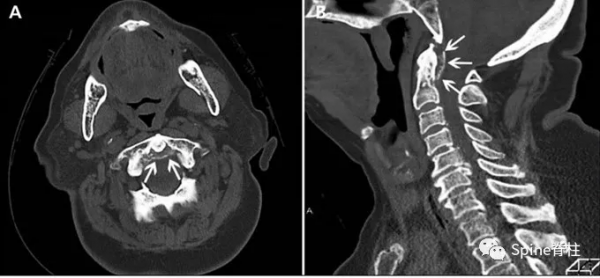

齒狀突加冠綜合徵(Crowned dens syndrome)是指患者以急性頸痛伴隨頸椎活動受限就診,常伴發熱,且影像學上表現為齒狀突上方或周圍出現大小不一、高密度、不規則的鈣沉積影,但主要發生在齒狀突後側。因影像學徵象猶如齒突戴上了一頂皇冠(如下圖),因而得名齒狀突加冠綜合徵,是因鈣鹽晶體在樞椎齒突周圍軟組織中沉積形成的。早在1985年,Bouvet等 (Arthritis Rheum, 1985) 首先報道此病。

頸椎CT冠狀位重建顯示猶如齒突戴上了一頂皇冠

故得名齒狀突加冠綜合徵

一位88歲女性患者,主訴急性頸痛伴發熱2個月入院。體溫波動在38-39.3℃,無視力模糊,無神經及脊髓壓迫徵象。頸椎CT+矢狀位重建顯示寰椎橫韌帶的曲線狀鈣化(圖A,箭頭所示),線性鈣化(圖B,箭頭所示),以及齒狀突周圍的冠狀鈣沉積(圖C,箭頭所示)。給予短期非甾體抗炎藥和潑尼松龍(15mg/d)後,其上述症狀完全緩解。同時,作者指出這類疾病通常不需要長期用藥。

一位84歲的男性患者,因“急性頸痛、僵硬伴發熱”就診。查體:頸椎向各個方向活動受限,無明顯神經病變體徵。實驗室檢查:血沉及C反應蛋白偏高。頸椎CT平掃提示齒狀突橫韌帶鈣化(箭頭所示),從而診斷為齒狀突加冠綜合徵。給予洛索洛芬治療一週後,上述症狀完全緩解,而且炎性指標恢復正常。

患者女,76歲。無明顯誘因下出現頸部疼痛、僵硬伴發熱 3 d 入院 ,頸部疼痛呈間歇性,頸痛視覺模擬評分(VAS)為7分,體溫37.7~38.8℃,無四肢疼痛麻木,無行走不穩,二便正常。既往無痛風、類風溼關節炎病史。入院體檢:頸椎旋轉明顯受限,頸部肌肉僵硬,未查及明顯神經或脊髓損傷體徵。實驗室檢查:白細胞11.2×109/L,紅細胞沉降率35.4 mm/h,超敏C反應蛋白14.7 mg/L,類風溼因子及降鈣素原正常。頸椎CT平掃示齒狀突後側寰椎橫韌帶弧形鈣化(左圖箭頭)和豎直線樣鈣化(右圖箭頭)。依據患者病史、體徵及輔助檢查,齒狀突加冠綜合徵可基本診斷。入院後給予氯諾昔康 8 mg靜脈滴注每日2次,地塞米松起始量10 mg靜脈滴注每日1次,3日後改為5mg/d。連續治療5 d後,患者入院時症狀明顯緩解,複查白細胞、紅細胞沉降率、超敏C反應蛋白均恢復正常。隨訪半年,未有頸痛伴發熱症狀出現。